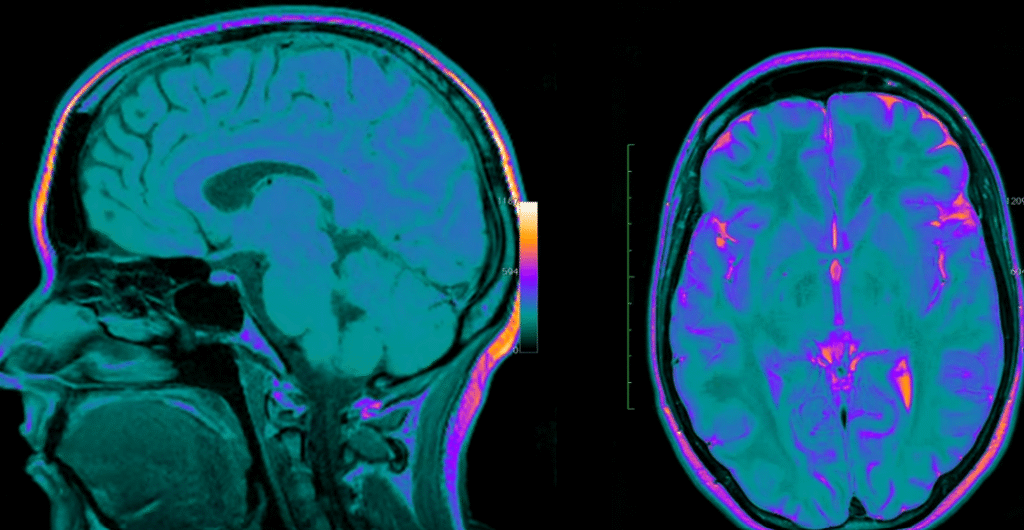

The brain is a live network that constantly reshapes, prunes, and strengthens connections every time we learn a new ability or remember a concept. It is not a static collection of memories. Neuroscience has demonstrated that all information is constructed by biological rewiring, which is quite similar to how a sculptor forms clay—purposeful, patient, and teeming with possibility.

Therefore, learning is the active building of understanding rather than the passive absorption of knowledge. The brain’s capacity to reorganize itself over the course of a lifetime is known as neuroplasticity, according to neuroscientists. It implies that development is not limited to childhood. Adults are also capable of learning new languages, changing their mental landscapes, and regaining cognitive function following an injury. This realization has had a significant impact on personal growth, treatment, and education by serving as a constant reminder that possibility is limitless.